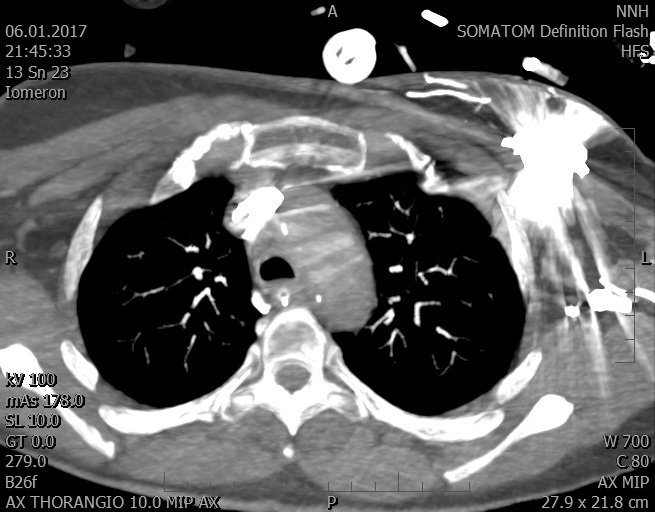

Video 2 - Echokardiograficky byla zjištěna těžká dysfunkce dilatační levé komory s nezvětšenou pravou komorou.Pro nejasnou příčinu zástavy jsme provedli i vyšetření výpočetní tomografií (CT), které vyloučilo plicní embolizaci (série 1 - soubory na konci článku). V den přijetí při přetrvávající oběhové nestabilitě byla nemocná opakovaně defibrilována pro fibrilaci komor se stabilizací rytmu po podání amiodaronu a mesocainu. Dle hemodynamických měření se jednalo o těžký kombinovaný šok. Vstupní laboratorní vyšetření bylo bez větších pozoruhodností. Posléze jsme doplnili anamnézu od příbuzných a zjistili, že pacientka užila do dvou hodin před srdeční zástavou první tabletu amoxicilinu na lehký respirační infekt. Při nevýtěžnosti vstupních vyšetření a nových anamnestických informacích jsme doplnili 14 hodin po kolapsu vyšetření koncentrace tryptázy v séru, která byla extrémně zvýšena (tabulka 2), což nás vedlo k podezření na anafylaxi.